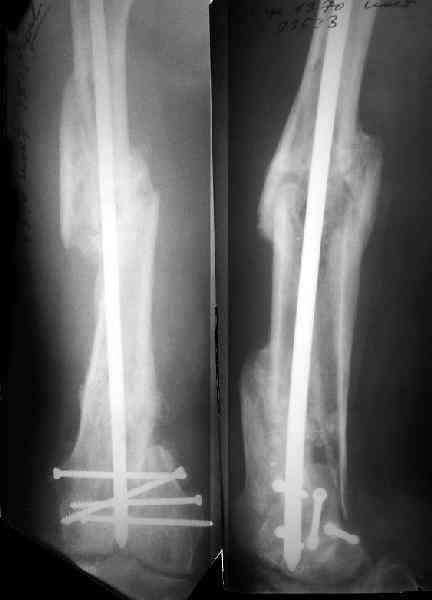

По прямой проекции неплохо. Что за стержень?

Антеградный остеосинтез при дистальных переломах бедра мы применяем давно, этот материал обобщен в канд. диссертации Александра Виноградского.

Примеры приложены.

Алекс, как Вы можете говорить, что "по прямой проекции неплохо"!? :( Гвоздь в суставе !!!

Снимаю свои претензии. На втором из снимков, которыми Вы хвастаетесь, гвоздь тоже в суставе, и ничего :(

И вообще мне кажется, что представленный ОС не допустим:1. стержень в суставе,2. неправильная длинна винтов, 3. ось конечности неправильная, 4. циркулярная гипсовая повязка после ОС?????

-1. стержень в суставе,

Это не критично, в межмышелковой борозде,не на опроной поверхности, выступает из субхондральной кости, не факт что из хряща.Про надколенник Александр Николаевич уже писал.

-2. неправильная длинна винтов,

и толщина тоже. При такой длине хочется помощнее.

-3. ось конечности неправильная,

Вполне прилично. Если в боковой проекции рекувации нет. Где кстати боковая, хочется спросить у постмейкера.

- 4. циркулярная гипсовая повязка после ОС?????

К сожалению, автор умалчивает. Думается, что в данном случае можно и без гипса.

Приносим извенения за недостаток информации. Выкладываю все снимки. Стержень фирмы НПО ДЕОСТ(г.Пущино-на-оке)

Это результат через полгода. К сожалению, пациент больше не приезжал на контрольный осмотр.